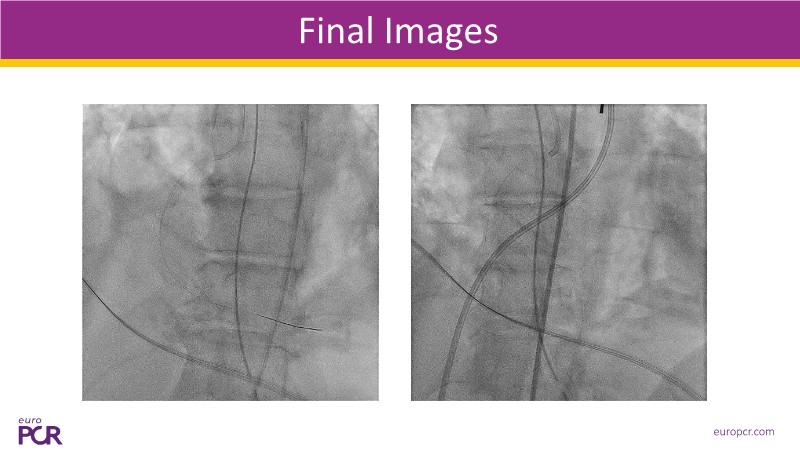

Explore how real-world data and evolving evidence are reshaping IV antithrombotic strategies in complex PCI. This EuroPCR 2025 session brings together urgent clinical cases—including STEMI patients in shock—and highlights key insights from the SMILE registry. Learn how transition protocols from cangrelor to oral P2Y12 inhibitors are applied in practice, compare approaches across Europe and the US, and get a forward-looking perspective on what’s next for IV therapies in 2025. A must-watch for anyone managing high-risk PCI.